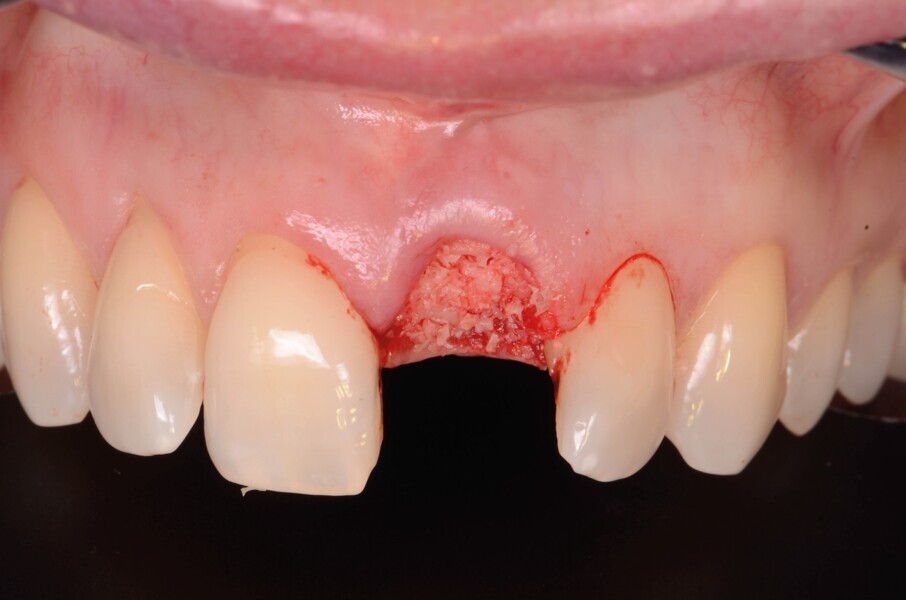

L’alvéole est ensuite comblée par un matériau allogénique (poudre d’os PHOENIX, TBF ; Fig. 5 ) qui est légèrement compacte puis recouvert d’une membrane L-PRF pour protéger le greffon (Fig. 6). La membrane L-PRF a un rôle essentiellement mécanique qui permet de prévenir toute dispersion ultérieure du matériau de greffe dans les premières phases de la cicatrisation, jusqu’à la formation d’un caillot sanguin stable.

Fig. 5c : L’alvéole est comblée par un greffon allogénique (poudre d’os PHOENIX, TBF).

Fig. 5d : L’alvéole est comblée par un greffon allogénique (poudre d’os PHOENIX, TBF).

Fig. 6 : L’alvéole est recouverte avec une membrane L-PRF.